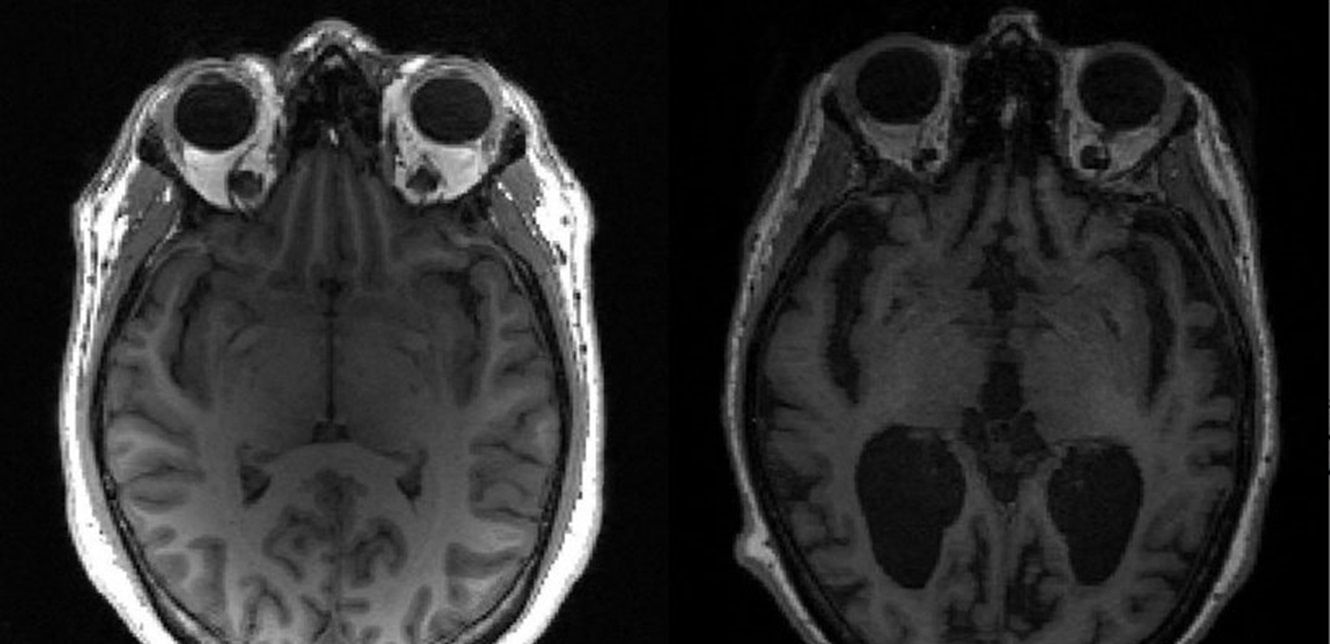

وفي مختبر راينهارت بجامعة بوسطن الأميركية، درس باحثون تأثيرات تقنية تسمى (TACS) على تحفيز الوظائف العقلية المختلفة لدى المرضى والأشخاص الأصحاء.

وخلال هذا الإجراء، يرتدي الأشخاص غطاءً مرنا مدمجا بأقطاب توفر تيارات كهربائية ضعيفة تتأرجح بترددات محددة إلى فروة الرأس. من خلال تطبيق هذه التيارات الخاضعة للرقابة على مناطق معينة من المخ، من الممكن تغيير "نشاط الدماغ"، عن طريق تحفيز "الخلايا العصبية".

وفحص الباحثون "الوظائف المعرفية المحددة، مثل الذاكرة والانتباه"، ولاحظوا أن (TACS) قد حسنت "الوظائف التنفيذية" للمخ. ولاحظ الباحثون أيضا تحسينات في القدرة على الانتباه وحفظ المعلومات لفترات زمنية قصيرة وطويلة.